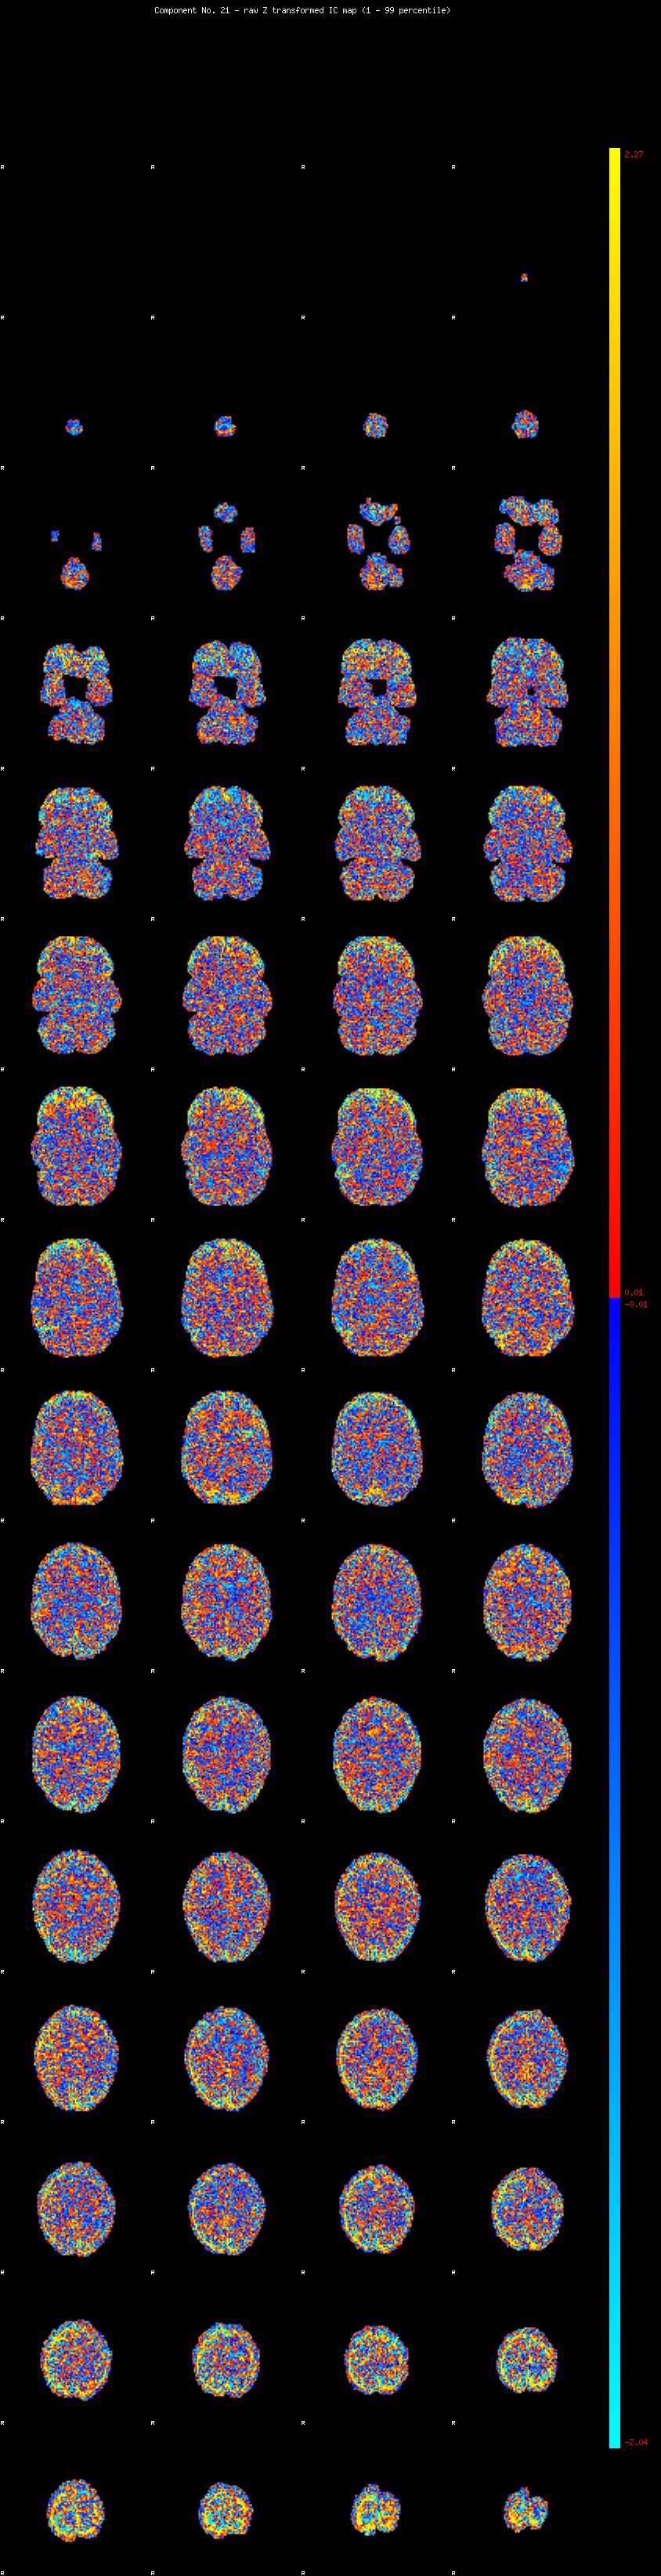

IC_21 Mixture Model fit

Means : 0.000000 2.365380 -2.280119

Vars : 1.000000 1.511392 1.333577

Prop. : 0.890140 0.066636 0.043223